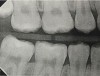

Fig 3. Three thin soft dental picks were used simultaneously for SDF proximal surface saturations in a teenaged patient (Fig 3). After 60 seconds, the treated regions were covered with 5% fluoride varnish (Fig 4). A comparison can be seen of pre-SDF-treatment bitewing films (Fig 5) and 8-month post-SDF bitewing films (Fig 6) for the patient shown in Fig 3 and Fig 4. Radiolucencies were similar or improved, except for contact of maxillary first and second molars.

Fig 5. Three thin soft dental picks were used simultaneously for SDF proximal surface saturations in a teenaged patient (Fig 3). After 60 seconds, the treated regions were covered with 5% fluoride varnish (Fig 4). A comparison can be seen of pre-SDF-treatment bitewing films (Fig 5) and 8-month post-SDF bitewing films (Fig 6) for the patient shown in Fig 3 and Fig 4. Radiolucencies were similar or improved, except for contact of maxillary first and second molars.

Interproximal insertion of SDF is demonstrated in different patients in Figure 3 through Figure 11. Various diameters and brands of soft dental picks may be used depending on the closeness of the proximal surfaces and ease of insertion; for example, some picks are designed for use in wider spaces between teeth. This protocol also offers versatility. Figure 3, for example, shows the simultaneous use of three thin soft dental picks to saturate proximal surfaces with SDF in a teenaged patient; the treated regions were subsequently covered with fluoride varnish (Figure 4). This patient was initially treated in April 2019 (Figure 5), with an identical re-application 3 months later. As shown in Figure 6, the December 2019 bitewing film revealed good results with the possible exception of the contact regions of the maxillary first and second molars. New SDF application was completed in the December appointment.

The senior author's (TPC) private practice experience with soft-tip insertion of SDF into contacting proximal surfaces of teeth is that most beginning proximal surface caries lesions cease to progress, as evidenced by subsequent bitewing radiographic comparisons (Figure 3 through Figure 6, Figure 12 through Figure 18). The chances for success vary, however, depending on frequency of application, subsequent flossing by patients or adults flossing younger children, diet control, individual mouth chemistries, and use of fluorides for the topical effect. It must also be emphasized that office staff should make extensive efforts to inform children and parents that subsequent daily flossing is needed to accompany SDF treatments; otherwise, SDF applications will only delay the inevitable progression of caries. Flossing methods should be demonstrated for patients and for parents so they may see how to floss younger children. Showing them enlarged graphic photographs of flossing results may be helpful in this regard. Parents and patients should be made aware that if interproximal dental plaque accumulations persist without daily interruption by flossing, the acid insult will eventually take its toll on the proximal surfaces and caries lesions will progress to the point where restorative intervention may be required.